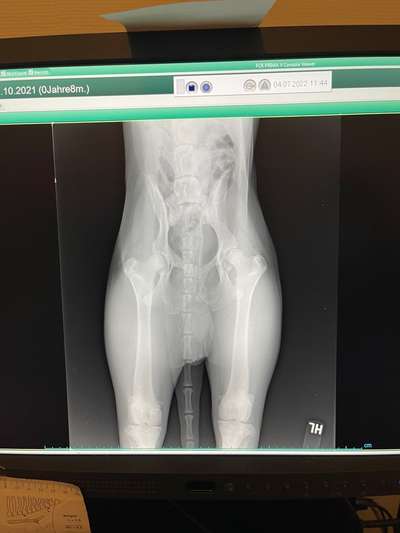

Hallo Zusammen, Mein Hund Tyson( 8 Monate alt )hat seit 3 Wochen Probleme mit seiner Hüfte.. ( Vorallem linke Seite )Bein laufen wackelt sie stark hin und her. Heute habe ich beim Tierarzt Röntgen Bilder von seiner Hüfte machen lassen. Mir haben sie gesagt dass ich in eine Spezialklinik in Duisburg fahren soll. Hat jemand Erfahrungen damit ? Oder vielleicht schonmal eine ähnliche Situation? Kann mir jemand weiterhelfen? :(

Die Röntgenbilder sind nicht gut, da der Hund nicht korrekt gelagert ist.

Ich hab schon viele Röntgenbilder gesehen. Könnte eine C Hüfte sein, da operiert man nicht!

Dazu sind die Bilder zu schlecht um es hier zu erkennen.

Uii das sieht aber nach einer starken HD aus 😔 geht zu einem Experten und lasst euch beraten, dein Schnuff hat sicher arge Schmerzen.

Ja, bin kein Experte, aber es sieht aus als hätte der Hund beim Röntgen schief gelegen.

Und genau abklären was das ist, also neue Röntgenbilder machen und einen Experte soll das beurteilen.

Könnte er sich ausgetenkt haben? Ich seh nämlich auf dem röntgenbild auch so schief aus... Vlt mal zum Chiropraktik mit dem hund